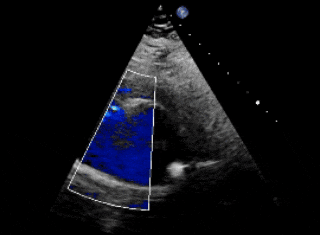

超声下可见双盘面骑跨

封堵器形态良好,基本无残余分流

本例患者于外院体检时发现心脏异常,升主动脉造影初步提示破口约8mm。由于患者抵抗力较低,如植入镍钛合金封堵器,术后需终身预防感染性心内膜炎,因此外院曾建议行外科手术修补。为进一步明确破口情况,术前团队对其进行了详尽的超声及造影评估,确认破口直径约为5mm,血流通向右房。考虑到破口位置靠近瓣膜,且可降解封堵器能够实现生理性修复,术后不留异物,无需终身预防感染性心内膜炎,本次手术最终选用ABFDQ-II 10全降解封堵器进行封堵。该封堵器材料柔韧,植入后可自适应周围结构及组织运动,不易影响或磨损瓣膜功能。术中释放后封堵器形态稳定,瓣上造影显示基本无残余分流,主动脉瓣启闭正常,手术取得圆满成功。术后1天超声复查提示瓦氏窦瘤封堵效果良好,封堵器位置及功能正常,患者恢复顺利,已康复出院。